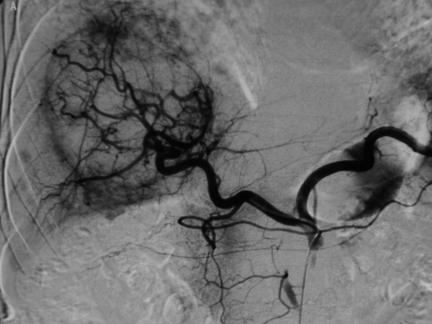

Embolisation has become an accepted modality of cancer treatment in patients with a variety of clinical scenarios. It is commonly used in clinical practice in the treatment of hepatocellular carcinoma, hepatic metastases from colorectal cancer and neuroendocrine tumours, and renal cell carcinoma. This review summarizes the current evidence for the efficacy of embolotherapy in these clinical settings, together with the associated complications.

栓塞治疗已成为多种临床情况下癌症治疗的一种可接受的方式。在临床实践中,它通常用于治疗肝细胞癌、结直肠癌肝转移和神经内分泌肿瘤以及肾细胞癌。本文综述了栓塞治疗在这些临床情况下的疗效的现有证据,以及相关的并发症。